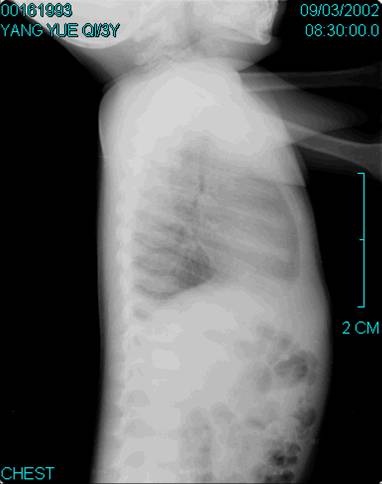

照片名称:胸椎压缩性骨折